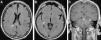

Ataxia y nistagmo de origen infrecuente

Ataxia and nystagmus of unusual origin